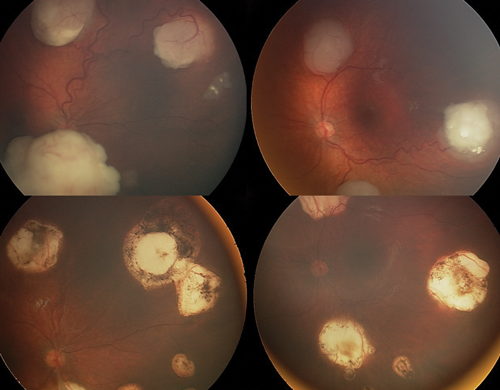

Laser treatment: Laser treatment is suitable for primary treatment of smaller tumours, or larger tumours after they have been shrunk to a treatable size with chemotherapy (chemoreduction). Laser treatment is, however, not effective for vitreous seeds (Figure 1).

Figure 1: Tumours before (above) and after treatment with chemotherapy and laser (below).